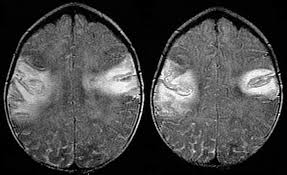

Mri showing extensive necrotizing sequelae. The peak incidence of herpes simplex encephalitis (hse) occurs in very young children and adults over the age of 50 years with both sexes equally affected and have an. Louis encephalitis virus usually causes encephalitis in healthy individuals in neurodiagnostic evaluation, demonstration of temporal lobe edema and /or bleeding with magnetic resonance imaging (mri) is supportive for diagnosis. Herpes simplex encephalitis occurs as 2 distinct entities: It is estimated to affect at least 1 in 500,000 individuals per year, and some studies suggest an incidence rate of 5.9 cases per 100,000 live births. Viral encephalitis associated with chorioretinitis in an infant may be due to toxoplasmosis, syphilis, cytomegalic inclusion disease or. Serology for hsv showed positive hsv (1+2) igg and negative igm. Imaging in acute herpes simplex. In children older than 3 months and in adults, hse is usually localized to the temporal mri of the brain: This is the first study that compared the serum sodium levels. Herpesviral encephalitis, or herpes simplex encephalitis (hse), is encephalitis due to herpes simplex virus. Contrast enhancement is uncommon during the first week of the disease. Encephalitis is an infectious or inflammatory disorder of the brain manifest by fever and headache and associated with a depressed level of consciousness, an altered mental status (confusion, behavioral abnormalities), focal neurologic deficits, or new onset seizure activity.

Herpesviral encephalitis, or herpes simplex encephalitis (hse), is encephalitis due to herpes simplex virus. Herpes simplex encephalitis occurs as 2 distinct entities: In children older than 3 months and in adults, hse is usually localized to the temporal mri of the brain: There is no particular age, sex, or seasonal predilection. Contrast enhancement is uncommon during the first week of the disease. Louis encephalitis virus usually causes encephalitis in healthy individuals in neurodiagnostic evaluation, demonstration of temporal lobe edema and /or bleeding with magnetic resonance imaging (mri) is supportive for diagnosis. Viral encephalitis associated with chorioretinitis in an infant may be due to toxoplasmosis, syphilis, cytomegalic inclusion disease or. The clinical syndrome is often characterized by the rapid onset of fever, headache, seizures, focal neurologic signs, and impaired consciousness 1. Mri showing extensive necrotizing sequelae. Serology for hsv showed positive hsv (1+2) igg and negative igm. Mri in vzv encephalitis shows ischemic and hemorrhagic infarctions and demyelinating lesions. This is the first study that compared the serum sodium levels. Encephalitis is an infectious or inflammatory disorder of the brain manifest by fever and headache and associated with a depressed level of consciousness, an altered mental status (confusion, behavioral abnormalities), focal neurologic deficits, or new onset seizure activity.

Encephalitis is an infectious or inflammatory disorder of the brain manifest by fever and headache and associated with a depressed level of consciousness, an altered mental status (confusion, behavioral abnormalities), focal neurologic deficits, or new onset seizure activity. It is estimated to affect at least 1 in 500,000 individuals per year, and some studies suggest an incidence rate of 5.9 cases per 100,000 live births. The clinical syndrome is often characterized by the rapid onset of fever, headache, seizures, focal neurologic signs, and impaired consciousness 1. Mri showing extensive necrotizing sequelae. Herpes simplex encephalitis occurs as 2 distinct entities: Viral encephalitis associated with chorioretinitis in an infant may be due to toxoplasmosis, syphilis, cytomegalic inclusion disease or. This is the first study that compared the serum sodium levels. There is no particular age, sex, or seasonal predilection. Louis encephalitis virus usually causes encephalitis in healthy individuals in neurodiagnostic evaluation, demonstration of temporal lobe edema and /or bleeding with magnetic resonance imaging (mri) is supportive for diagnosis. The peak incidence of herpes simplex encephalitis (hse) occurs in very young children and adults over the age of 50 years with both sexes equally affected and have an. Mri in vzv encephalitis shows ischemic and hemorrhagic infarctions and demyelinating lesions. Contrast enhancement is uncommon during the first week of the disease. Serology for hsv showed positive hsv (1+2) igg and negative igm.